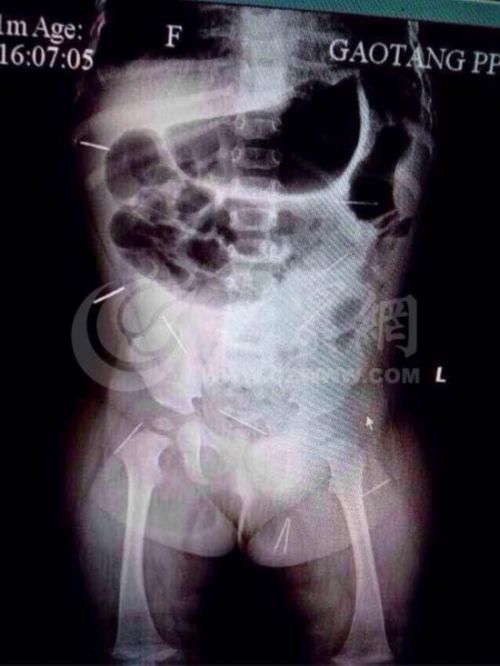

記者了解到,10月20日,紫萱的父母發現她有異常,遂帶她到高唐縣的醫院進行檢查。拍片的結果讓人大吃一驚,僅僅11個月大的小女孩兒,身體內竟然有12根鋼針狀的物體。從拍出的片子來看,12根鋼針插滿小紫萱身體臀部、腹腔、骨盆等各個部位,觸目驚心。據紫萱的父親范光生說,一個月之前,紫萱的母親在為她擦屁股時,紫萱總是哭鬧,當時從她的屁股上已經取出了4根針,當時以為是孩子玩耍時,自己不小心被針扎了,拔出來后,就沒當回事兒。